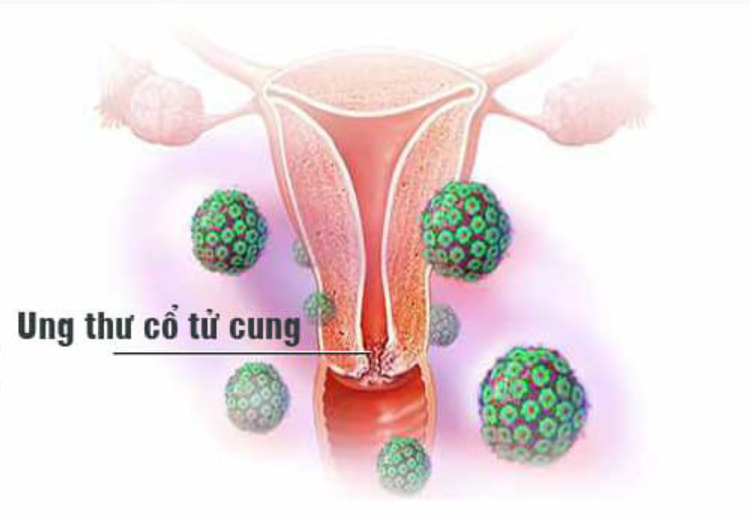

Các giai đoạn ung thư cổ tử cung

Ung thư cổ tử cung gồm các giai đoạn nào? Triệu chứng của ung thư cổ tử cung là gì? Cần làm gì để phòng tránh ung thư cổ tử cung?

18 tuổi có bị ung thư cổ tử cung không?

Ở bất kỳ độ tuổi nào cũng có nguy cơ bị ung thư cổ tử cung, tuy nhiên liệu 18 tuổi có bị ung thư cổ tử cung không? Cùng giải đáp câu hỏi này trong bài viết!

Bị ung thư cổ tử cung sống được bao lâu?

Bị ung thư cổ tử cung sống được bao lâu là câu hỏi mà rất nhiều bệnh nhân khi nhận được kết quả rất quan tâm. Khám phá ngay câu trả lời tại bài viết sau.

10 dấu hiệu ung thư cổ tử cung

Ung thư cổ tử cung là loại ung thư dễ gặp nhất ở phụ nữ. Cùng khám phá ngay 10 dấu hiệu ung thư cổ tử cung thường gặp để phòng tránh an toàn nhé!